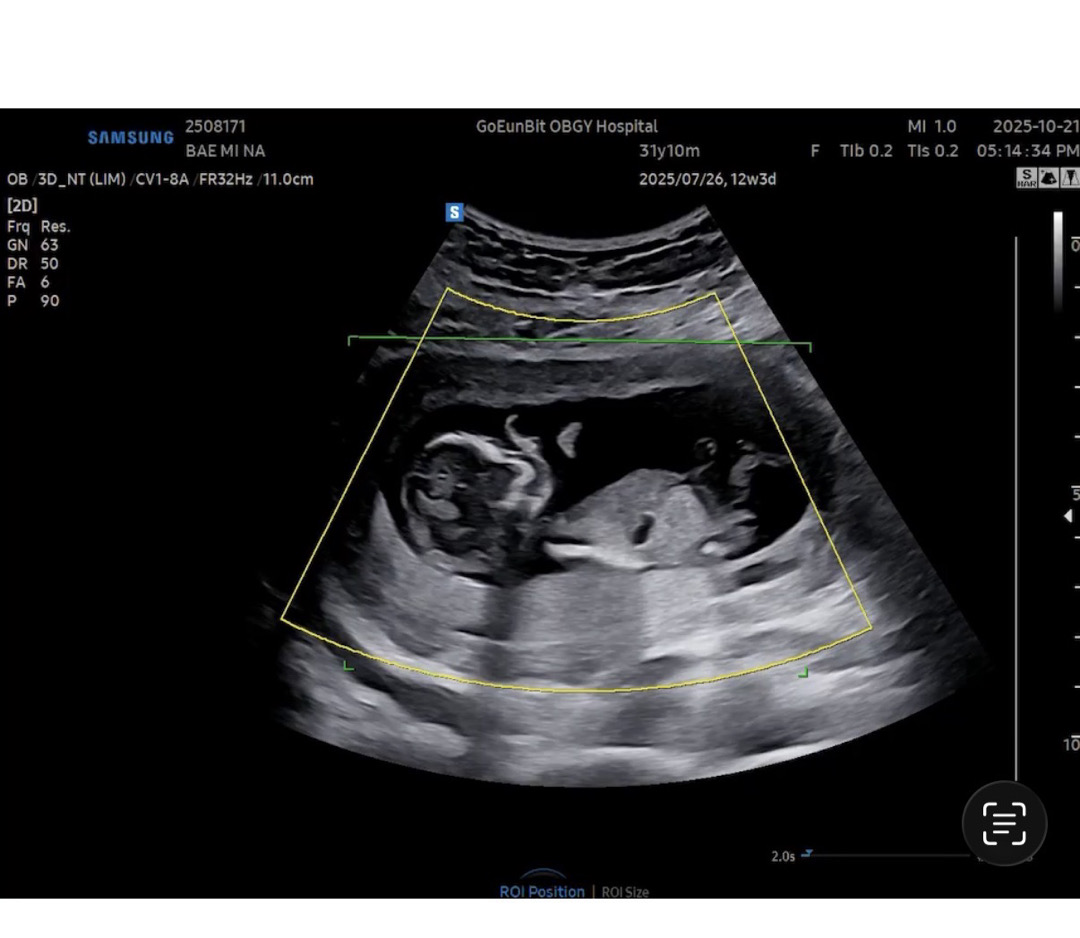

각도법 성별 질문드려요:)

12주 6일차에 초음파 보고왔는데 아무리 봐도 모르겠네요 ㅎㅎ 고수님들 알려주세요!